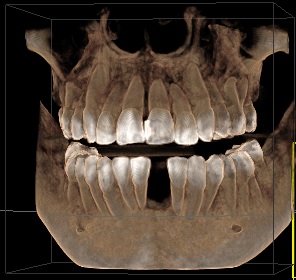

Edit Record Check our patient data records. Add patient information Patient Info Profile picture Last Name First Name Middle Name Birthdate Age Street Barangay City Country Zip Code Contact number Email Procedure 01/30/21 ICF - check up Feb 8,2021 - Implant 11/03/22- OP/OZONE/PAD feb,20,2021- removal of suture march 31,2021- LC 11 & 21 07/31/21 repair 41 zirconia resto 36CAOH/46 CAOH/43/34 OP June 4,2022 - OP / Xray 05/13/23- OP(Moderate); xray; ozone Oct 1 2023 op with air polisher noticed gum recession Removal of fiber splint on 42/43 05/07/24 Air polisher Xray OP 06/15/24 connective tissue graft harvested side: upper right quadrant w/ suture- monofilament absorbable 4/0 donor site: implant #41/32 buccal and lingual combination of monofilament absorbable 4/0 and nylon 6/0 non absorbable 06/22/24 check up 06/29/24 suture removal File raposa_donna_kelly_3.jpg File 2 raposa_donna_kelly_2.jpg File 3 raposa_donna_kelly_1.jpg File 4 donna_kelly.jpg File 5 june_42022.jpg File 6 raposa_donna.jpg File 7 raposa_donna_02.jpg File 8 img_2831.jpg File 9 File 10 File 11 File 12 File 13 File 14 File 15 File 16 File 17 File 18 File 19 File 20 Retain Record Retain Record Yes No Save Your Changes